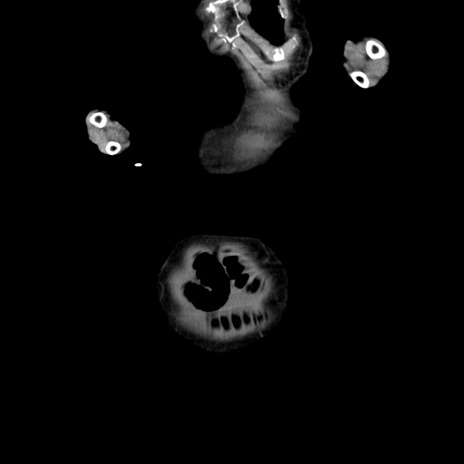

横断像

【症例】80歳代女性

【主訴】嘔吐、腹痛

【現病歴】数時間前より嘔吐あり。心窩部痛出現し、徐々に右下腹痛あり。その後も数回嘔吐あり救急搬送となる。

【既往歴】左大腿骨頚部骨折手術

【身体所見】腹部は膨隆しているが軟らかく圧痛なし。腸雑音はやや亢進。

【データ】WBC 12000、CRP 19.05